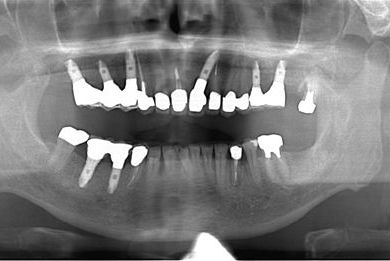

インプラントの症例写真 IMPLANT

骨再生インプラント治療

| 性別/年齢 | 男性 / 58歳 | ||||||||||||||||||||||||||||||||

| 主訴 | 上前歯欠損部のインプラント治療を希望。 | ||||||||||||||||||||||||||||||||

| 治療方針 | 右上奥はソケットリフトにて上顎洞拳上してインプラント埋入を可能にし、上顎前歯部は骨再生法によりインプラント治療を行う。その他、補綴により口腔内全体の機能的審美的回復を行う。 | ||||||||||||||||||||||||||||||||

| 治療内容 | インプラント8本(GBR、ソケットリフト)、ハイブリッドセラミッククラウン17本(セラミック用土台5本) | ||||||||||||||||||||||||||||||||

| 総治療費 | 4,077,076円 | ||||||||||||||||||||||||||||||||

| 治療期間 | 1年9ヶ月 |